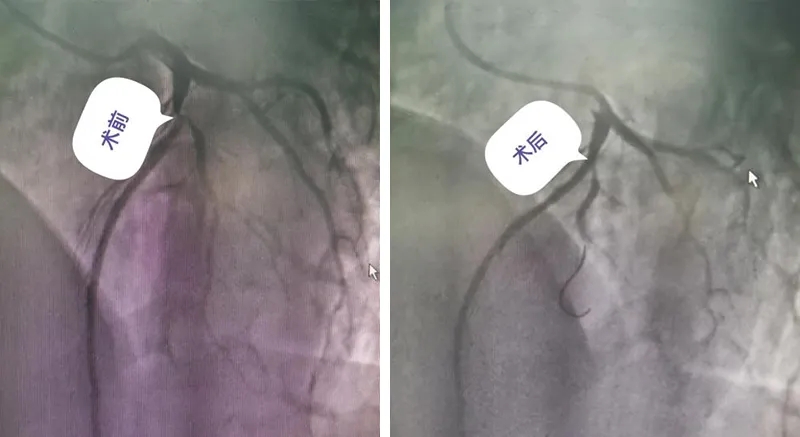

在救治上

手術(shù)團隊考慮

患者都比較年輕

沒有采用支架植入

而是采用

冠狀動脈內(nèi)

藥物球囊介入治療

讓心臟血流恢復(fù)正常

胸悶癥狀消失